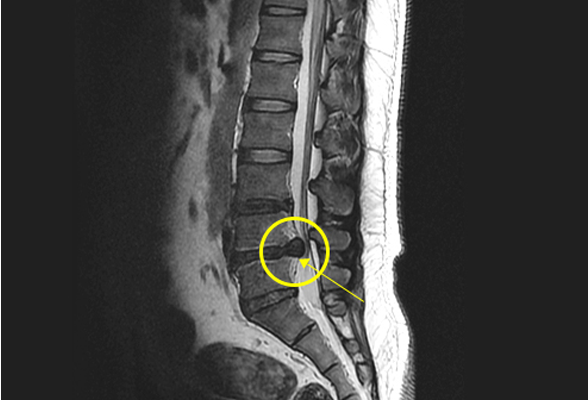

허리 디스크

척추뼈와 척추뼈 사이에서 뼈가 부딪히는 것을 막아주고,

충격을 흡수하는 원반 모양의 물질을 말합니다.디스크에 지속해서 힘이 가해지거나 외부 충격이 있게 되면,

디스크가 돌출되어 다리로 가는 신경을 누르고 통증이 발생합니다.

비수술 치료 : 약물치료, 주사치료, 물리치료, 도수치료, 신경성형술, 수핵성형술

수술치료 : 미세 현미경하 수핵 절제술, 최소침습 척추유합술